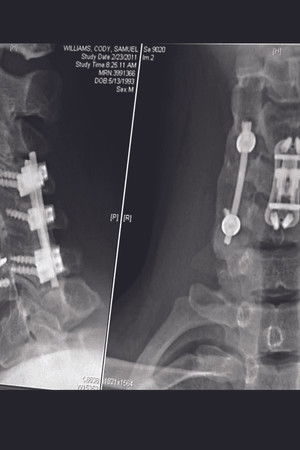

The compelling, heart-wrenching story of high school football star Chris Carnales, whose life changed when he became paralyzed after breaking his neck in a football game. Chris soon learned of others who suffered similar injuries and, with the help of his father, overcame tremendous pain to start an organization with one goal in mind: get immediate help to other victims and their families. He called it Gridiron Heroes.